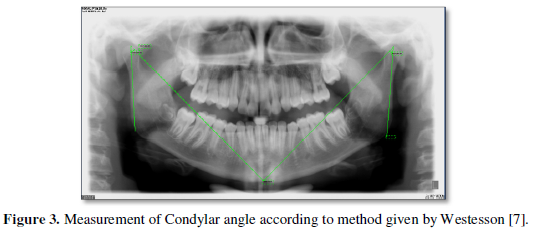

Condylar morphology was analyzed based on the classification of Oliveira-Santos [1] into flat, pointed, angled, round and other shapes (Figure 1).

The condylar height asymmetry index and condylar width asymmetry index was measured according to the formula given by Habets [5].

The asymmetry of the mandibular condyle reflects different development of the right and left sides. In 1987-89, Habets [5] proposed in three articles an OPG tracing method, that aimed to investigate any correlation between asymptomatic TMJs and condyle/ramus height and shape. The condylar width and condylar height asymmetry index in different age groups was found to be statistically significant, which was similar to previous studies done by Yáñez-Vico [13] in 2012. Also, high values observed indicating asymmetry in old age groups can be attributed to shape, angular and positional differences between the right and left condyles without any related malocclusion.

The horizontal angle of inclination of the mandibular condyle is important in maintaining the function of the temporomandibular joint [14]. The horizontal condylar angle was found to be significant among age groups indicating that condylar inclination is more among old age groups, especially in left condyles.

- Westesson PL, Liedberg J (1987) Horizontal condylar angle in relation to internal derangement of the temporomandibular joint. Oral Surg Oral Med Oral Pathol 64: 391-394.